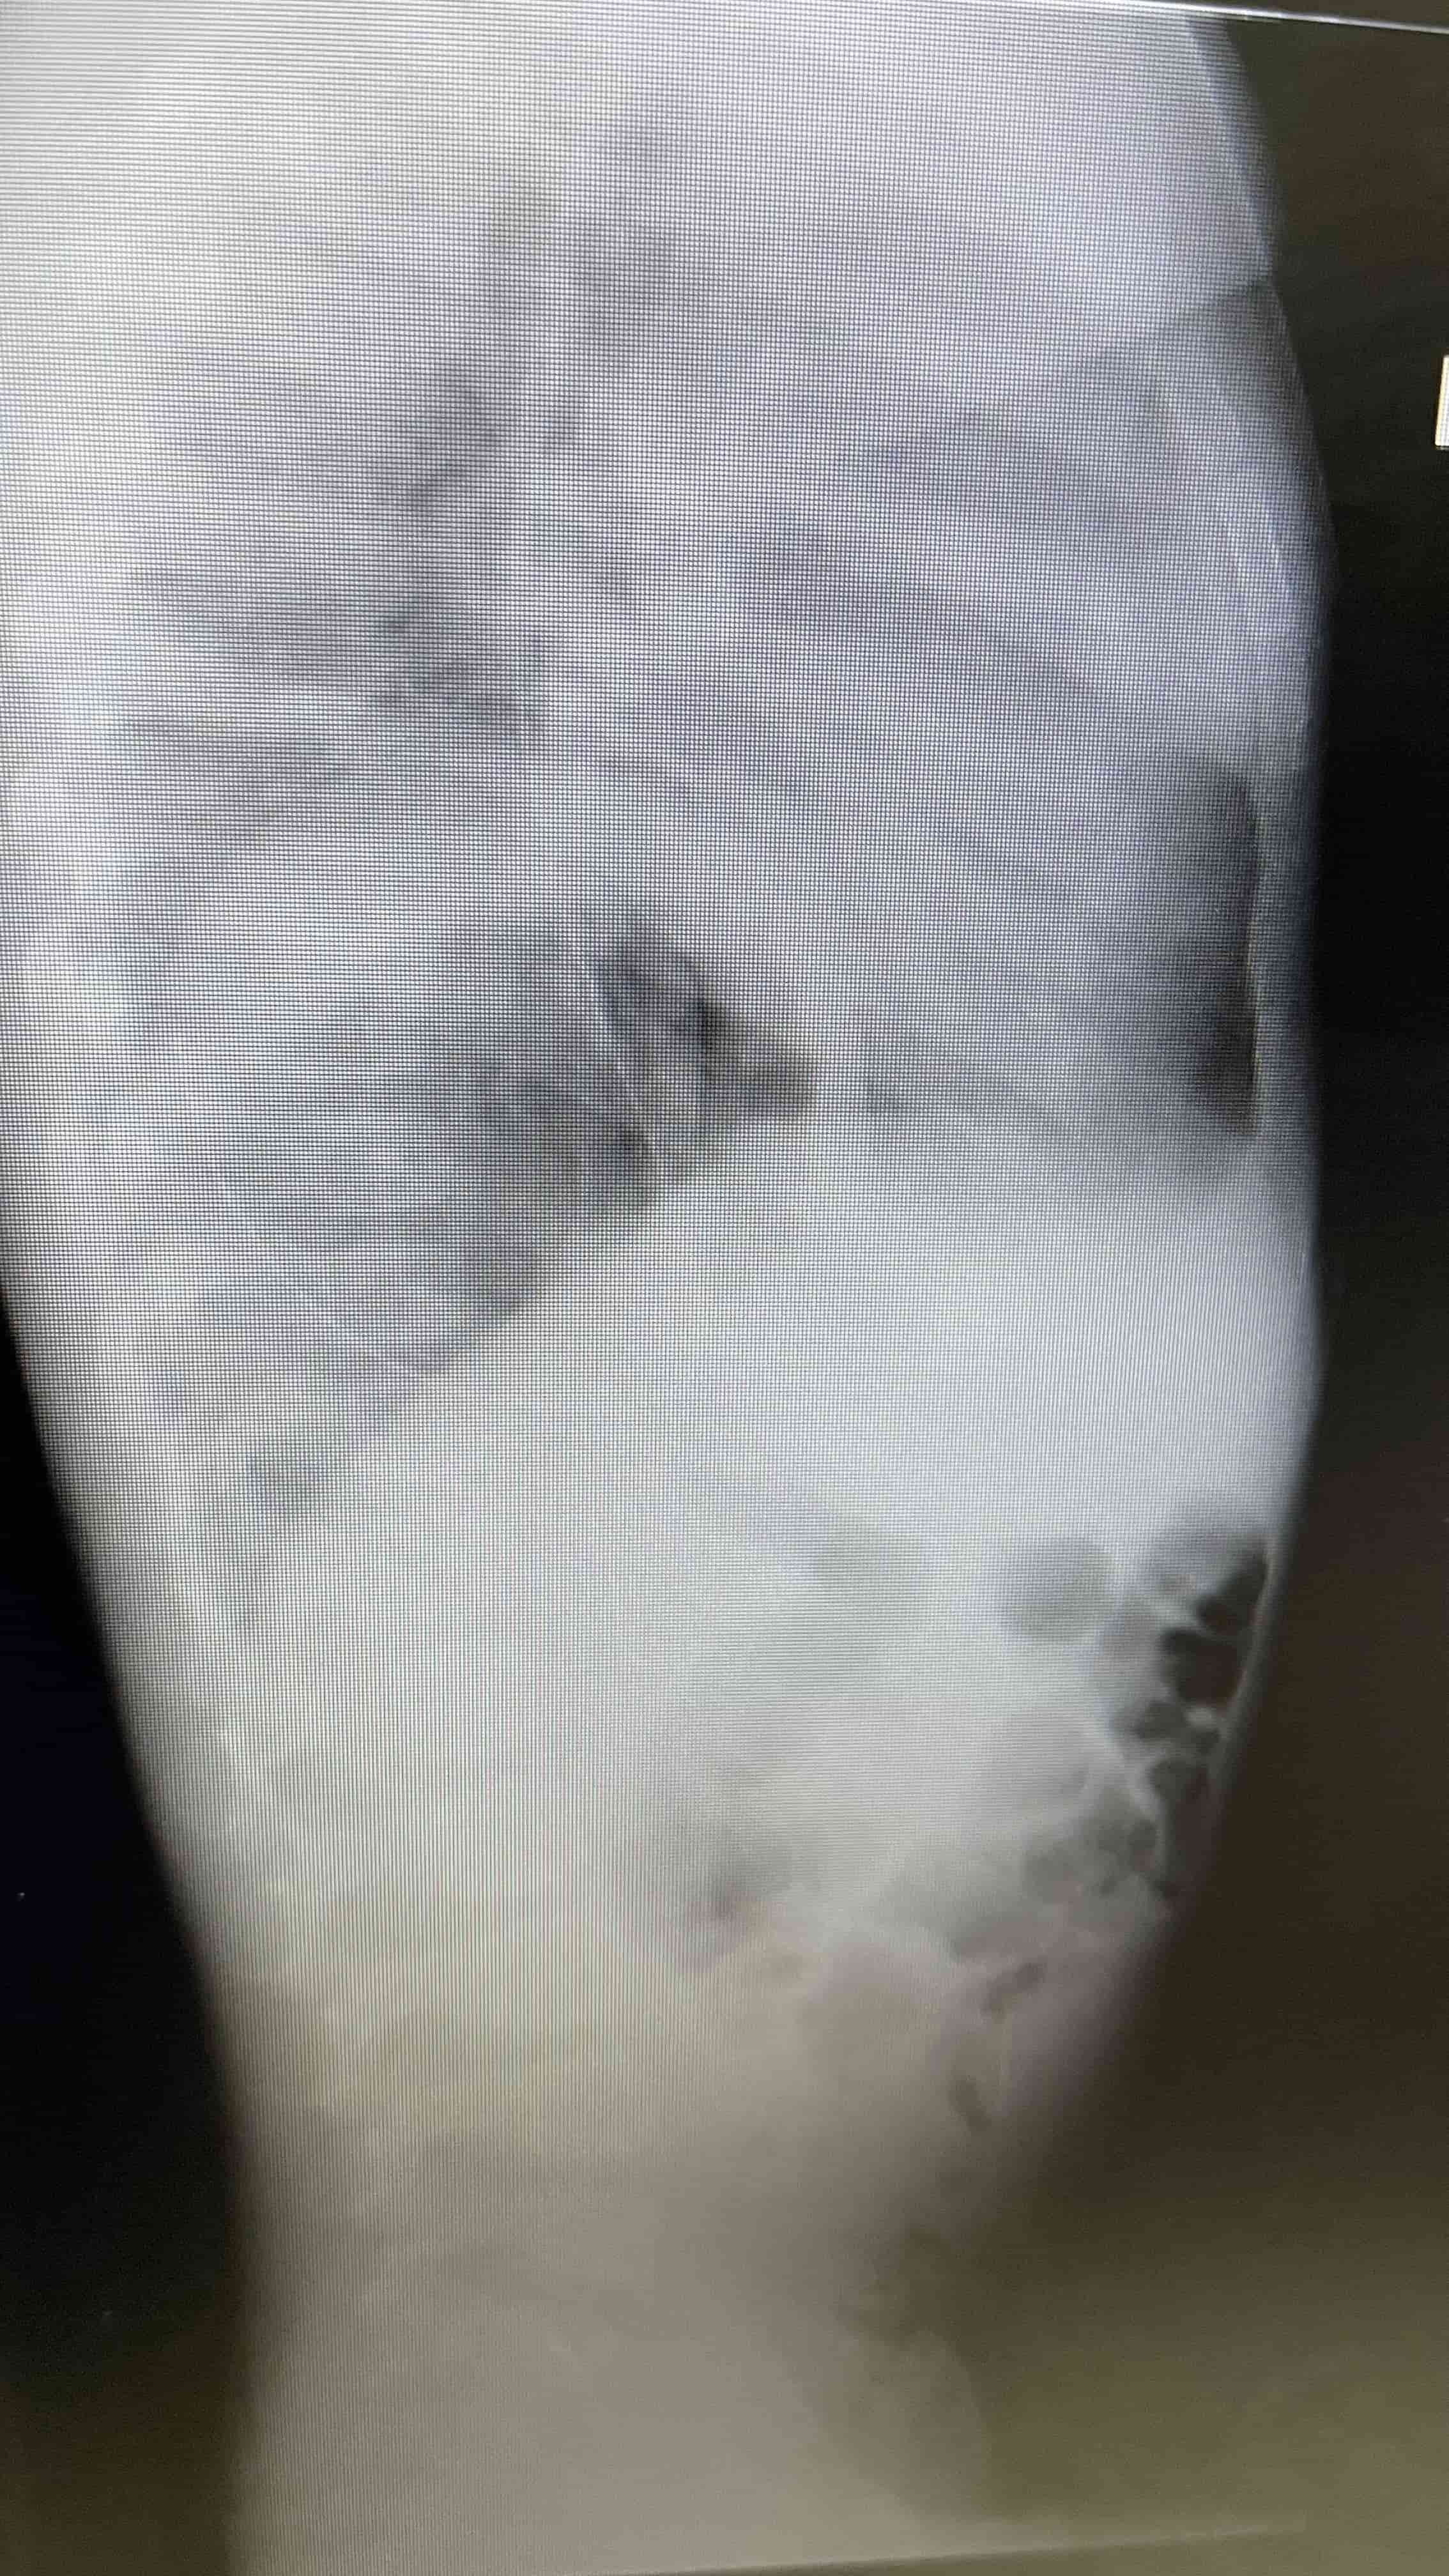

"Tuvimos que analizar rápidamente diagnósticos diferenciales para llegar al punto de lo que le estaba causando todos estos síntomas a la paciente. Se le realizaron placas de pecho y de abdomen, y ahí nos percatamos, que esta paciente teníauna herniadiafragmática y que gran parte de su estómago estaba distendido y dentro del hemitórax izquierdo, desplazando hacia el lado derecho del pecho las estructuras mediastinales. Fue entonces que llegamos a la confirmación del diagnóstico", detallaron.

"El estómago estaba muy distendido y lleno de líquido y aire, que empujaba las estructuras mediastinales y esto provocaba una disminución en la cantidad de sangre que llegaba al cuerpo. El radiólogo confirmó el diagnóstico , quien nos informó que tenía un gastrotórax a tensión, y esto demandó rápido el tratamiento de descompresión con un tubo nasogástrico", establecieron.

Médicos salvan la vida de infante con hernia diafragmática y gastrotórax a tensión  Placa lateral portable, se demuestra la hernia diafragmática. Médicos salvan la vida de infante con hernia diafragmática y gastrotórax a tensión  Radiografía de pecho y abdomen, luego de tratamiento con tubonasogástrico. Se demuestra mejoría marcada en desplazamiento deestructuras mediastinales. Médicos salvan la vida de infante con hernia diafragmática y gastrotórax a tensión  Placa de pecho portable luego de reparación quirúrgica del diafragma.